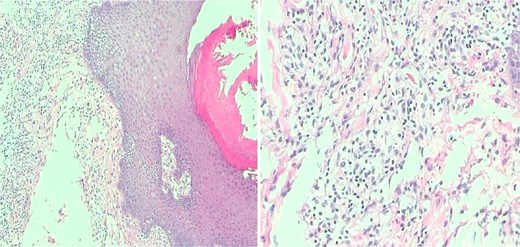

After thorough preoperative evaluation to exclude surgical and anaesthetic contraindications, the patient underwent local excision of perianal skin. During the procedure, hyperplastic, rough, and lichenified areas of perianal skin were meticulously resected. The incisions were designed in a tree-leaf pattern, with intervals of healthy skin tissue preserved between adjacent incisions to facilitate wound healing. Pathological examination of the resected tissue confirmed the presence of chronic dermatitis (Fig. 2). In the postoperative period, the wound was cleaned and dressed daily. By postoperative day 32, the wound had healed completely, with resolution of skin thickening and roughness, and complete alleviation of itching symptoms (Fig. 3). By day 40, the scars had faded significantly, and the patient had achieved full recovery (Fig. 4).

Intraoperative pathological examination of resected lesions demonstrating chronic skin inflammation.